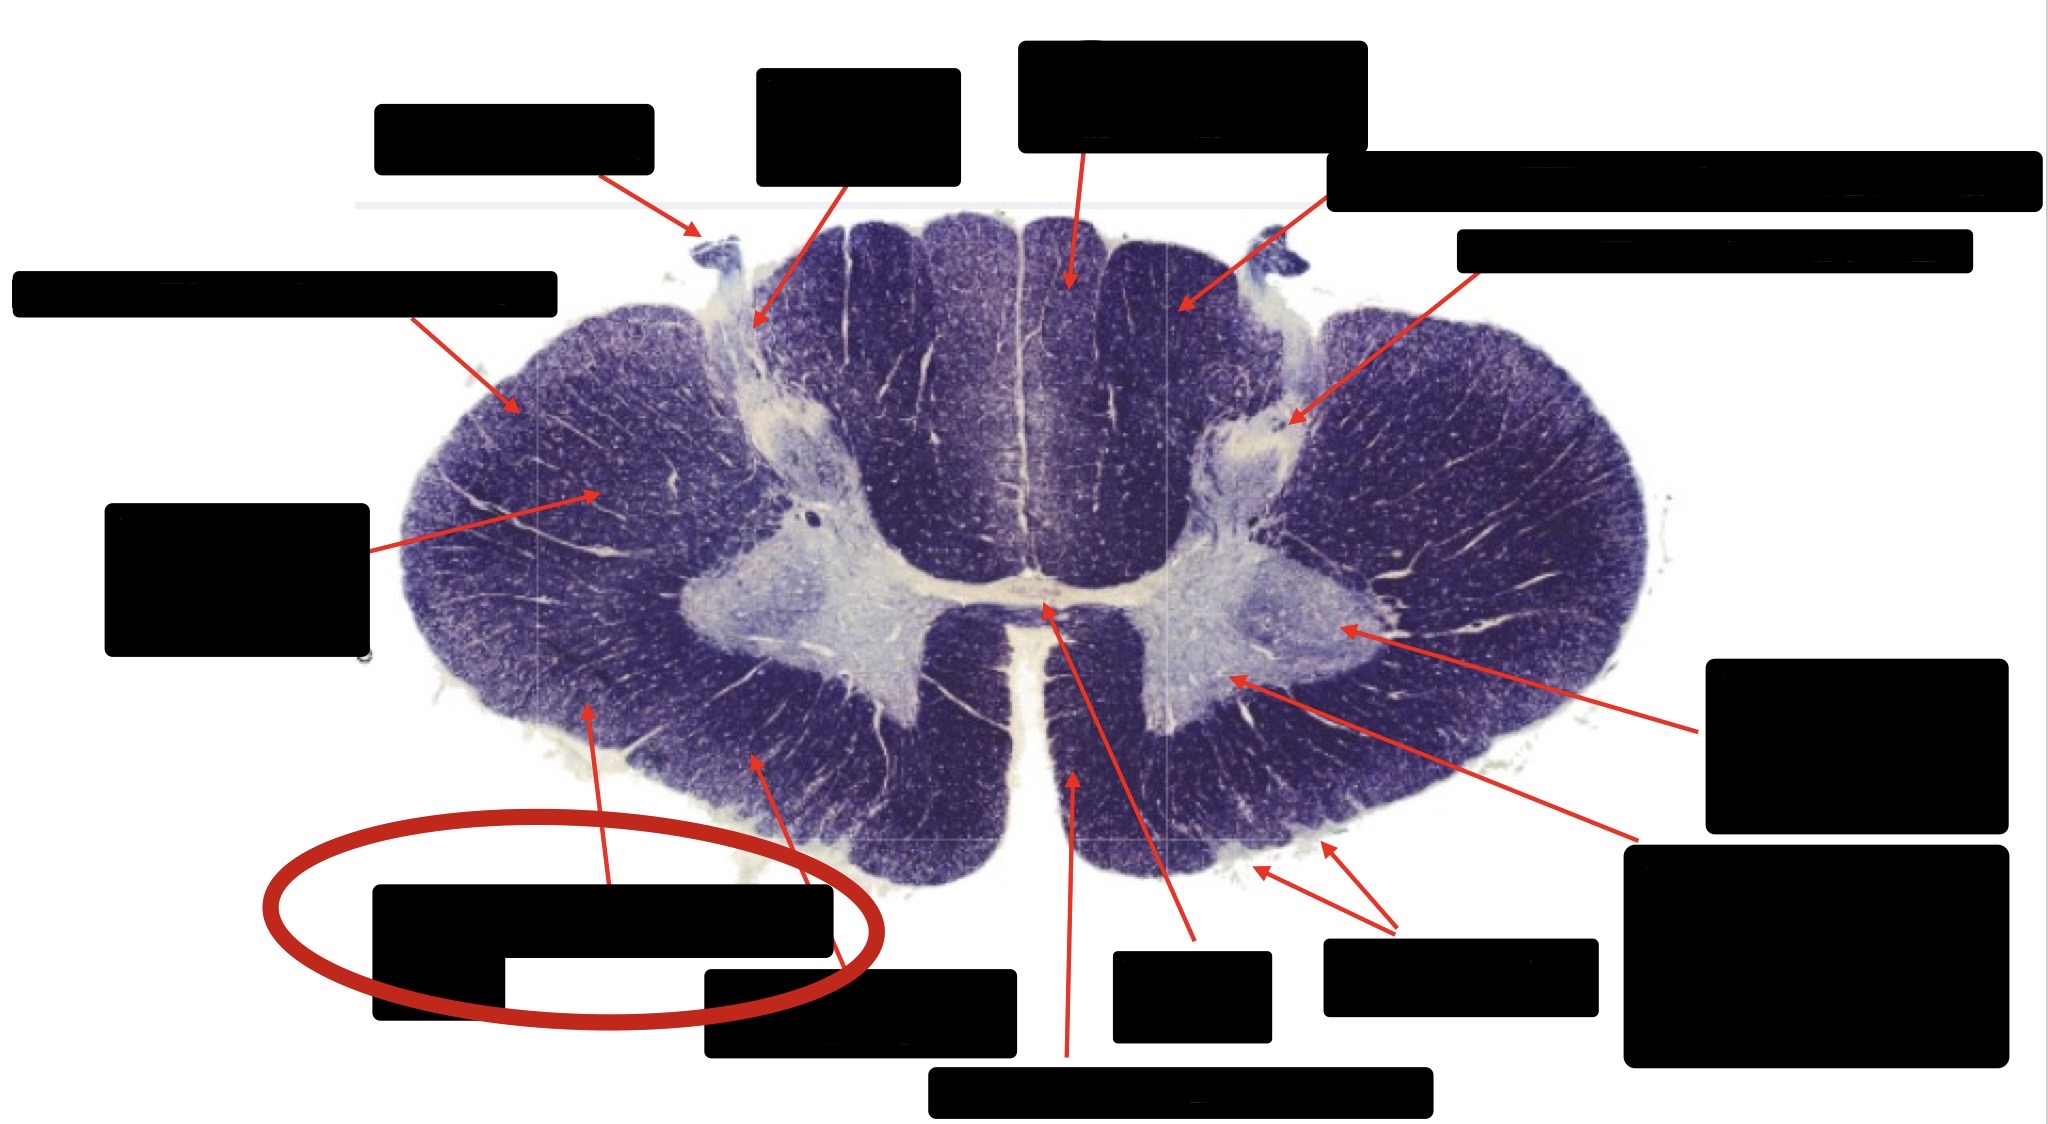

Posterior Column

Large Fiber Entry Zone

Posterior Spinocerebellar Tract

Clarke’s Nucleus

Anterior Spinocerebellar Tract

Ventral Root Fibers

Central Canal

Lissauer’s Tract & Small Fiber Entry Zone

Substantia Gelatinosa

Lateral Corticospinal Tract

Spinothalamic Tract

Anterior Horn Motor Neurons (Distal Muscles)

Anterior Horn Motor Neurons (Proximal Muscles)

Dorsal Rootlet

Lateral Horn

Spinothalmic Tract